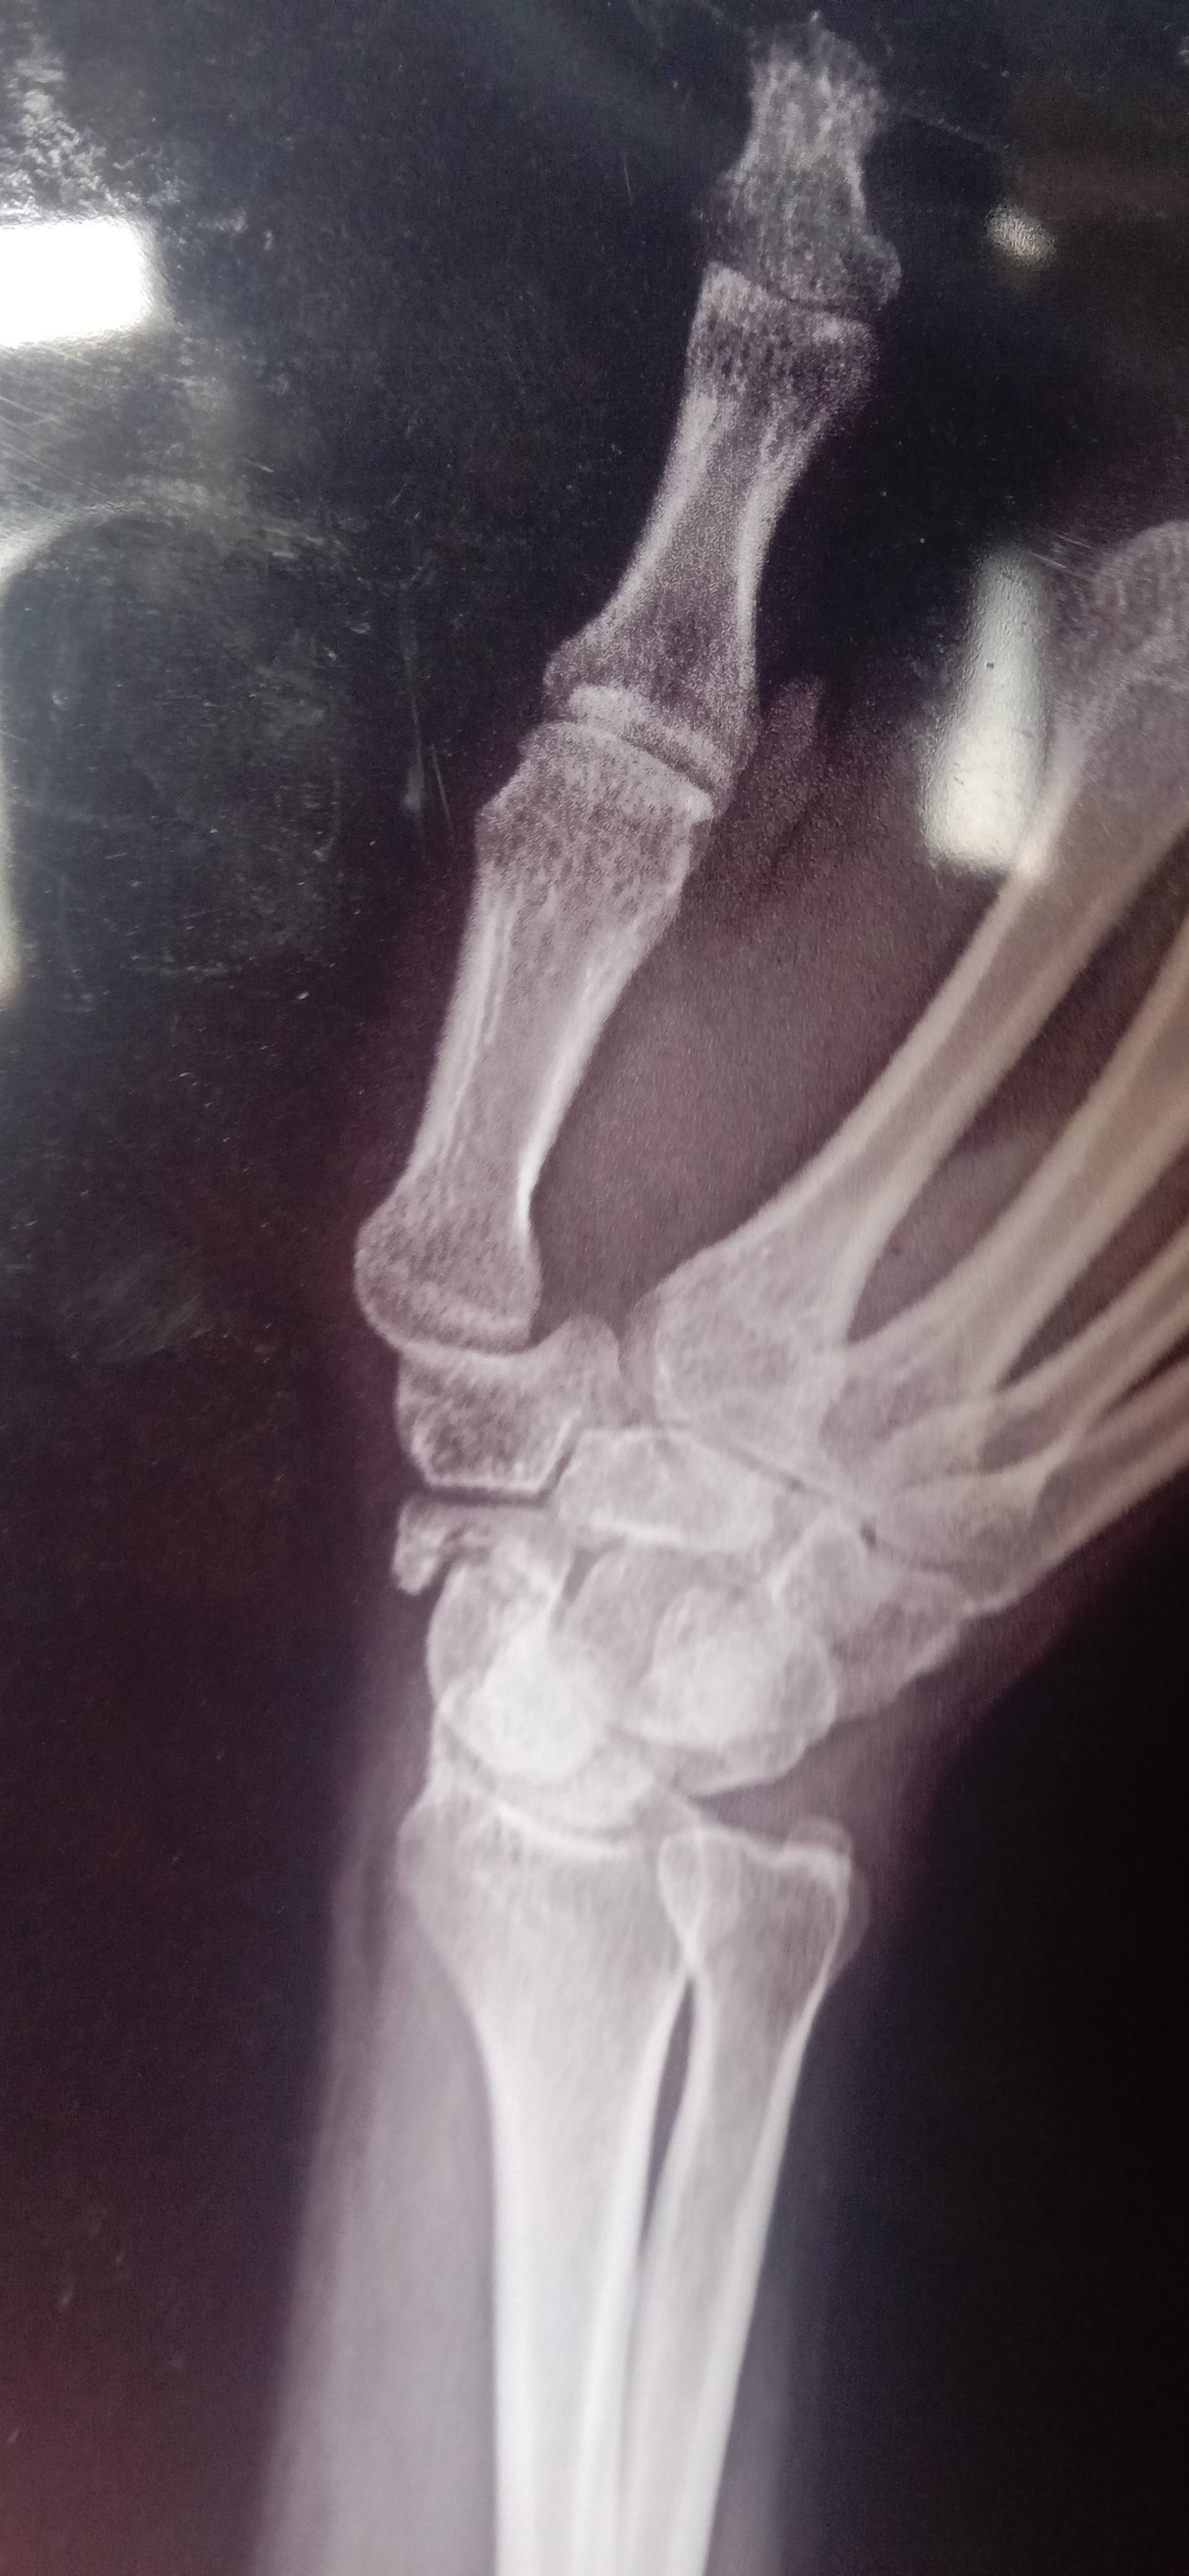

Sir mara scaphoid ko 4 months ho gye ha 2 months plaster laga tha pain nai hoti par moment karna ma parasani  ati ha

sir mara scaphoid ka fracture ha

Hlo sir mara scaphoid ka fracture ha

Hlo sir i have a fracture in my distal part of scaphoid